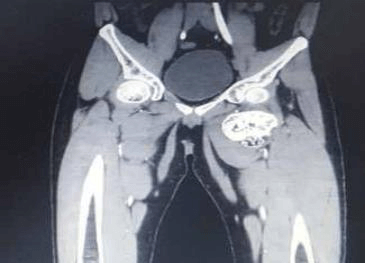

এখানে আমরা প্রক্সিমাল ফেমোরাল অস্টিওকন্ড্রোমার কারণে বাম নিতম্ব এবং উরুতে ব্যথা সহ একজন 28 বছর বয়সী পুরুষ উপস্থিত প্রতিবেদন করি। রেডিওগ্রাফ দেখায় ফুলকপির মতো ভর বাম প্রক্সিমাল ফিমার থেকে উদ্ভূত। বাম উরুর 3D CT স্ক্যান বিভাজনের কাছাকাছি ফেমোরাল জাহাজের সংকোচন পূর্ববর্তী স্থানচ্যুতি দেখায়। এই রোগীকে অস্ত্রোপচারের এন-ব্লক রিসেকশনের মাধ্যমে চিকিত্সা করা হয়েছিল এবং হিস্টোপ্যাথলজি অস্টিওকন্ড্রোমার ডায়াগনস্টিক ছিল।

অস্টিওকন্ড্রোমা বাম ফিমারের সাবট্রোচ্যান্টেরিক অঞ্চলের অ্যান্টেরো-মিডিয়াল দিকের উৎপত্তি যেখানে একটি বৃহৎ কার্টিলাজিনাস ক্যাপ সহ কম ট্রোক্যান্টারকে বিচ্ছিন্ন করে বিভাজনের কাছাকাছি ফেমোরাল জাহাজের সংকোচন পূর্ববর্তী স্থানচ্যুতি ঘটায়।

3D সিটি স্ক্যান